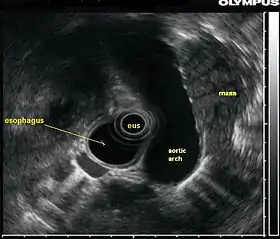

![]() صورة بالتنظير بالموجات فوق الصوتية، تظهر كتلة (في هذه الحالة سرطان الرئة) عن طريق إدخال مسبار التنظير بالموجات فوق الصوتية في مريء | |